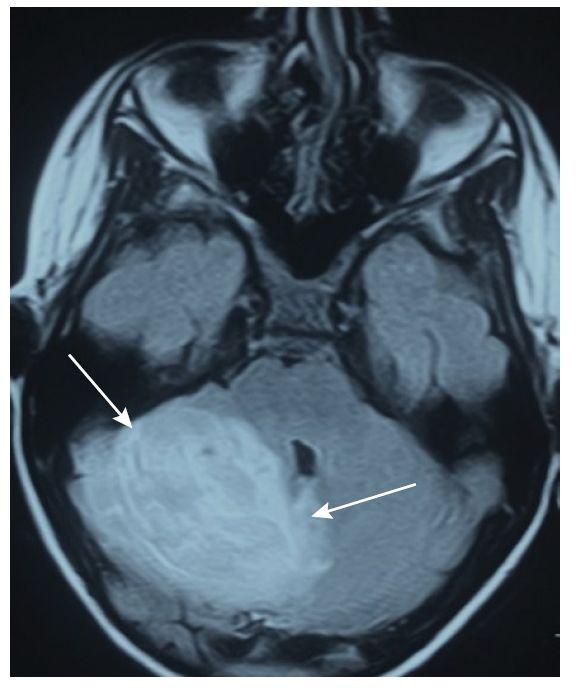

引起急性共济失调的其他疾病包括莱姆病,Whipple病,曲霉菌病,JC病毒,梅毒和克雅病等。亚急性共济失调和脑MRI异常(图1)可能是由JC病毒感染引起的。

图1 表现为亚急性小脑性共济失调的HIV患者。脑脊液PCR证实John Cunningham病毒感染(进行性多灶性白质脑病小脑型);A-B:T2WI和FLAIR可见小脑不对称高信号,累及左侧小脑半球和小脑中脚。